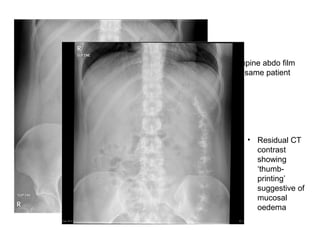

• 35 year old patient

with Crohn’s

disease, 3 days of

nausea and vomiting

• Erect film

• Supine abdo film

of same patient

• Residual CT

contrast

showing

‘thumb-

printing’

suggestive of

mucosal

oedema

• 35 yearold patient with Crohn’s disease, 3 days of nausea and vomiting • Erect film

• Supine abdofilm of same patient • Residual CT contrast showing ‘thumb- printing’ suggestive of mucosal oedema